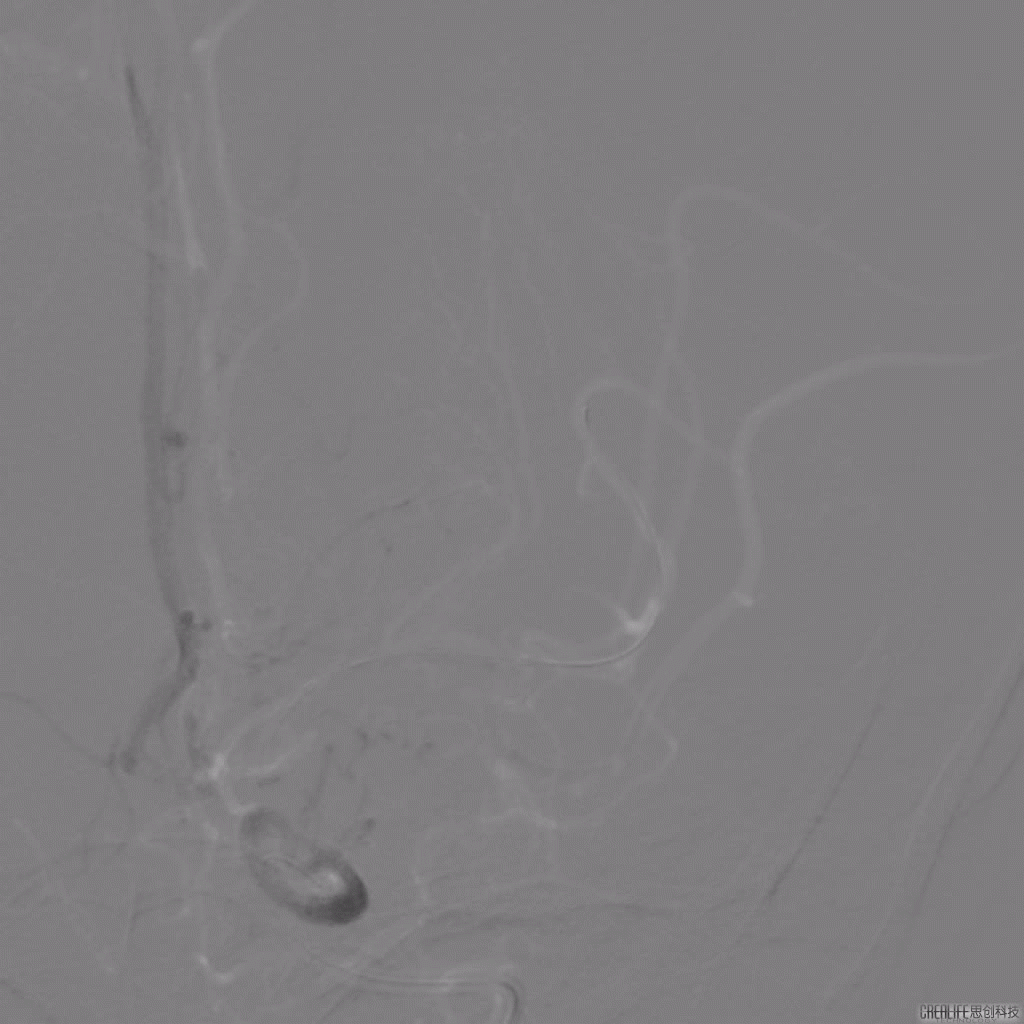

治疗过程

导引导管到位,导丝通过病变。

导丝怎么扩【载药时代 球扩天下】NOVA DES®颅内药物洗脱支架在颅内富穿支区域使用体会二例!_https://www.jmylbn.com_新闻资讯_第31张

支架释放后影像。